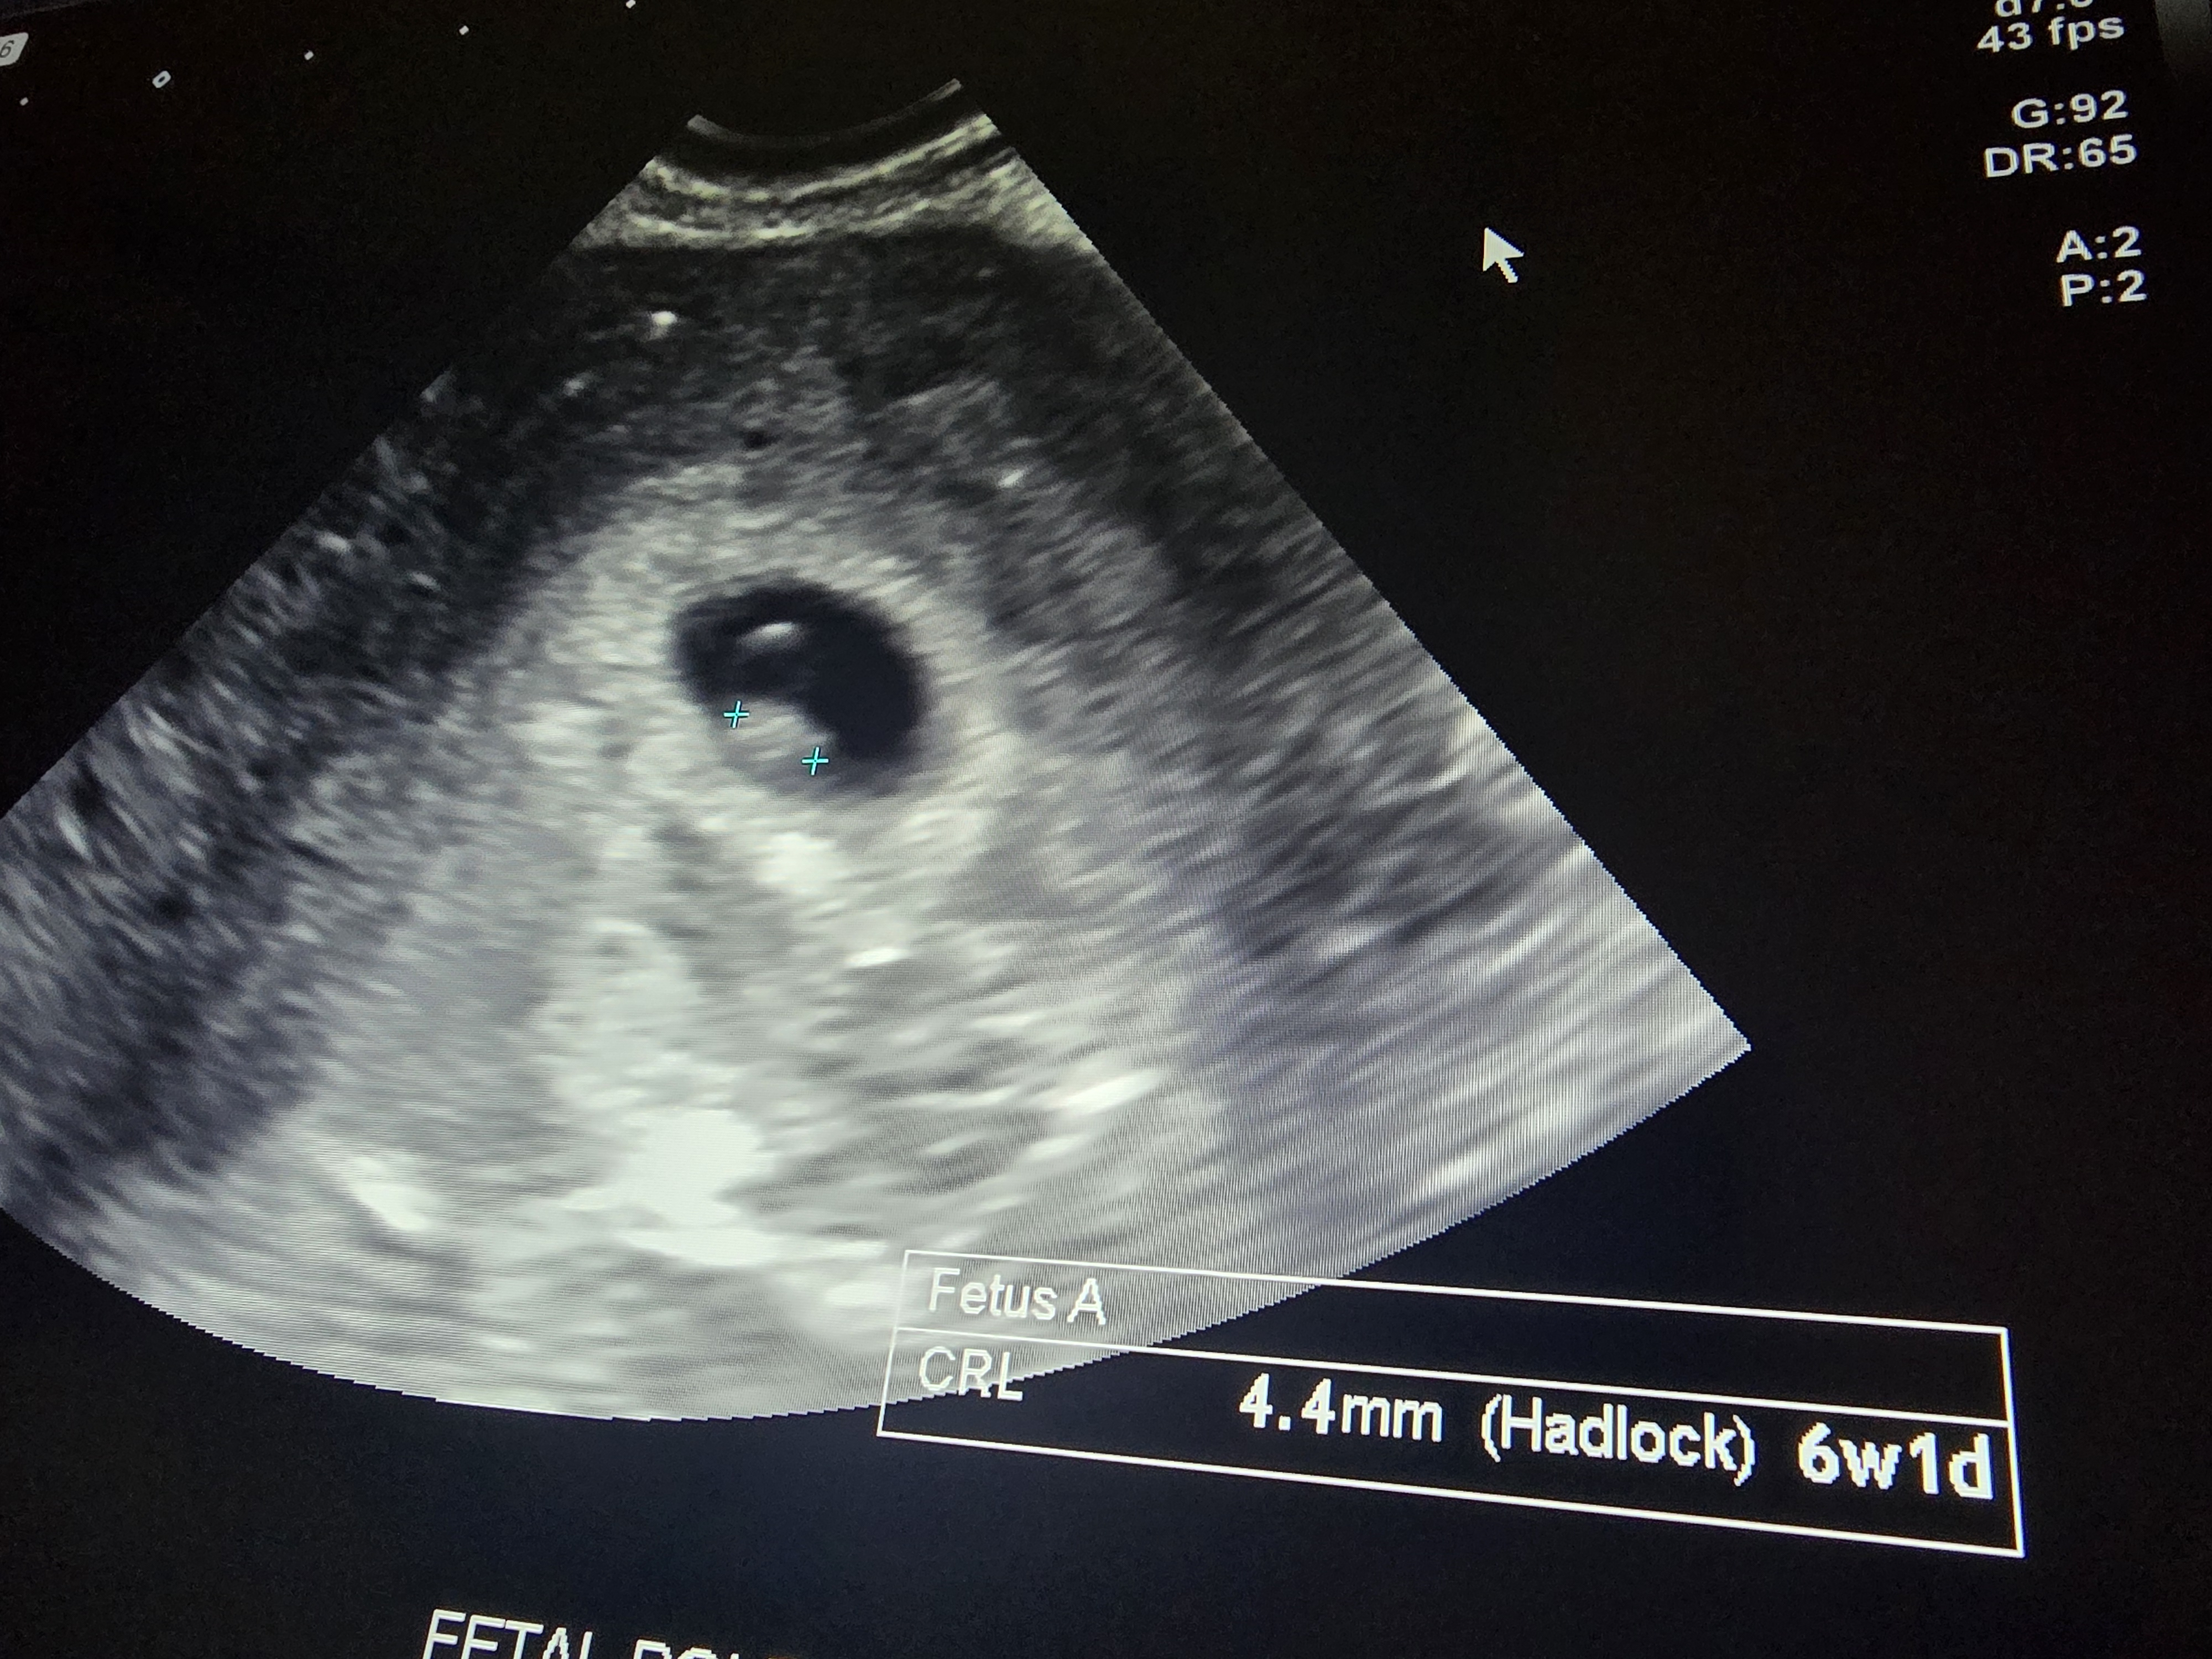

• Just got a call from Dr. She doesn't like how high the last reading was. So she is getting me in asap for ultrasound. She is concerned that it is ectopic. 😞

I have no other symptoms, no bleeding. So I'm just hoping I have high hormones. But I'm panicking and want answers.

So glad everything is okay! I had high numbers as well and turns out I am pregnant with twins!